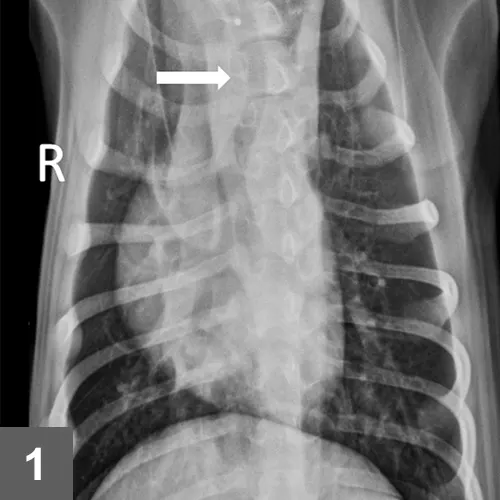

Packed cell volume, total protein, and whole blood glucose results were within normal limits. Right and left lateral and VD thoracic radiographs were taken (Figure 1).

FIGURE 1

VD view of thorax: Note leftward deviation of the trachea just cranial to the cardiac silhouette.

• Plain thoracic radiography is typically sufficient to diagnose vascular ring anomaly. Focal leftward deviation of the trachea near the cranial border of the heart in DV or VD radiographs is a reliable sign of PRAA.2